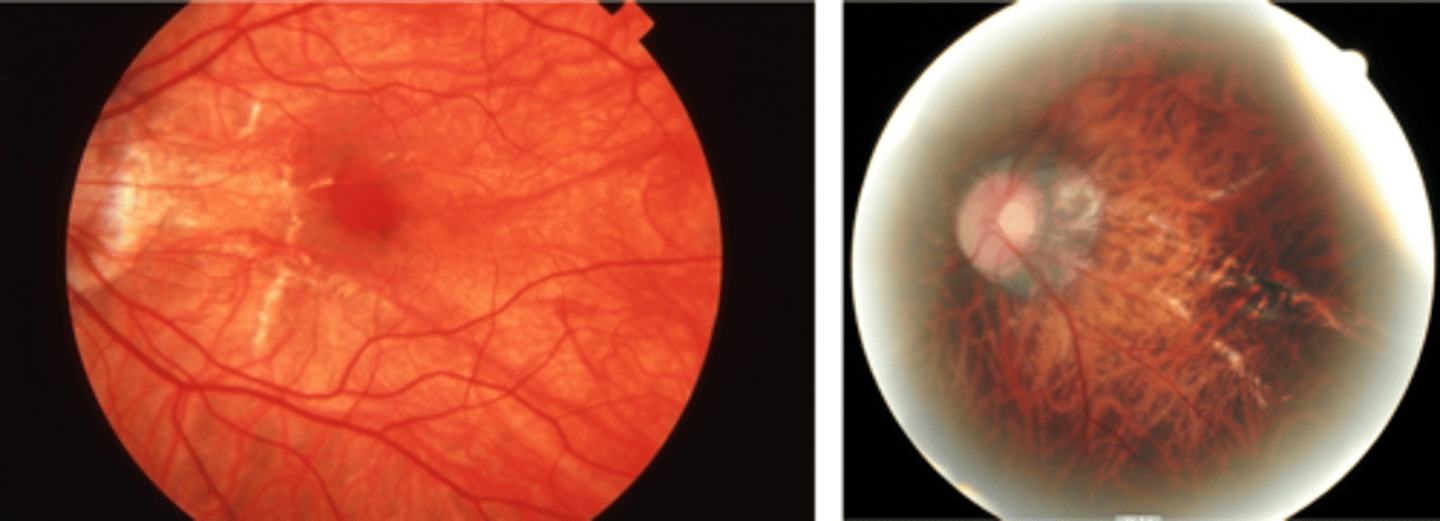

What finding of toxoplasmosis is seen in A/B?

retinitis turns into hazy scar with nerve pallor

What finding of toxoplasmosis is seen in C/D?

scarring overtime with VA loss/scotoma

What is seen in toxoplasmosis with OCT?

acute = retinitis = inflam, thickening of layers

acute = vitritis = dots and haze vitreous

chronic = necrotizing atrophy = scarring, thinning

What findings of toxoplasmosis are seen here?

retinal vasculitis

exudative scar

focal, hazy vitritis and retinitis